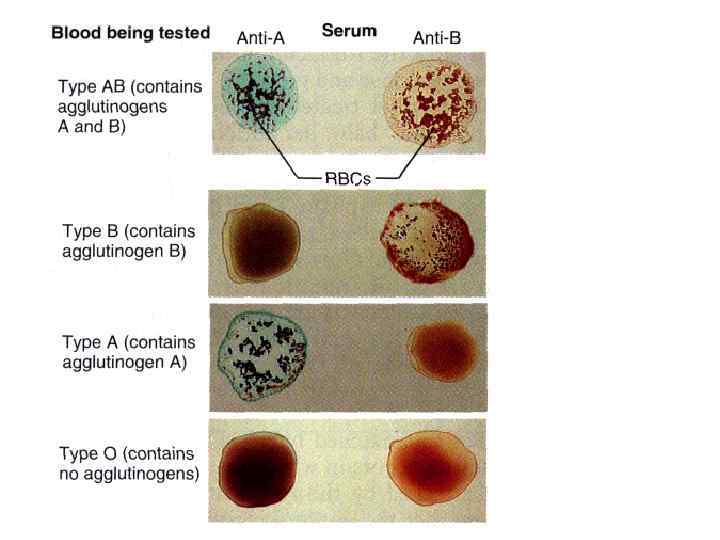

Вопрос 10 Система AB 0

Вопрос 10 Система AB 0

Стандартные сыворотки

Стандартные сыворотки